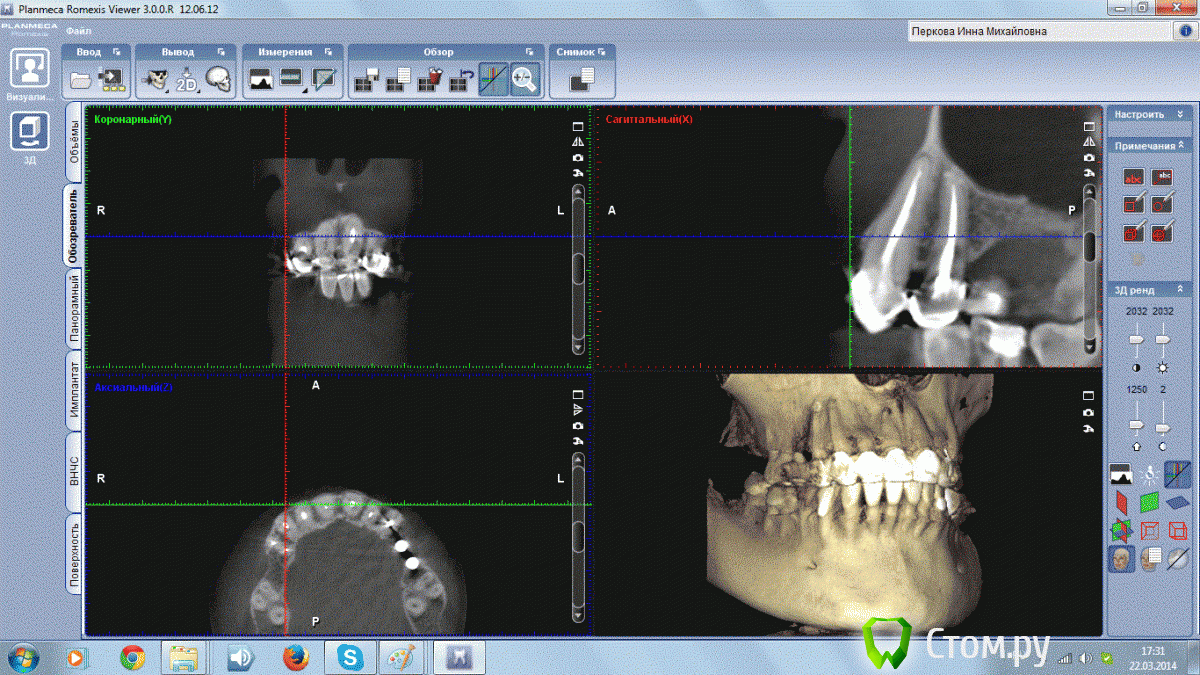

Инна Михайловна Опубликовано 22 марта, 2014 Поделиться Опубликовано 22 марта, 2014 (изменено) Добрый День!,У меня на 1 зубе обнаружили на КТ гранулему, но обнаружили уже после лечения канала. Долечен ли канал до верхушки? И посмотрите пожалуйста состояние остальных зубиков. Старая металлокерамика слетела, хочу делать новое протезирование. Изменено 22 марта, 2014 пользователем Инна Михайловна Ссылка на комментарий

Инна Михайловна Опубликовано 22 марта, 2014 Автор Поделиться Опубликовано 22 марта, 2014 Спасибо большое за скорый ответ! А на остальных зубах у корней небольшие затемнения? Эти зубы не надо перелечивать? Ссылка на комментарий

Гарриевич Опубликовано 23 марта, 2014 Поделиться Опубликовано 23 марта, 2014 Там где слетела старая керамика, зубы лечите и протезируйте Ссылка на комментарий